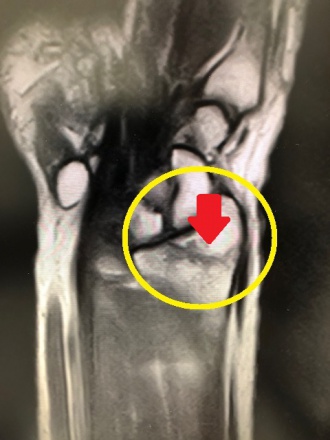

骨折の診断にMRIが有用です

最近は雪道で転倒して受診する患者さんが多いです。そんな場合、骨折の診断にMRIが有用です!

写真は手の関節の検査。

MRI画像(左)→ 骨折線(赤の矢印)がはっきり!